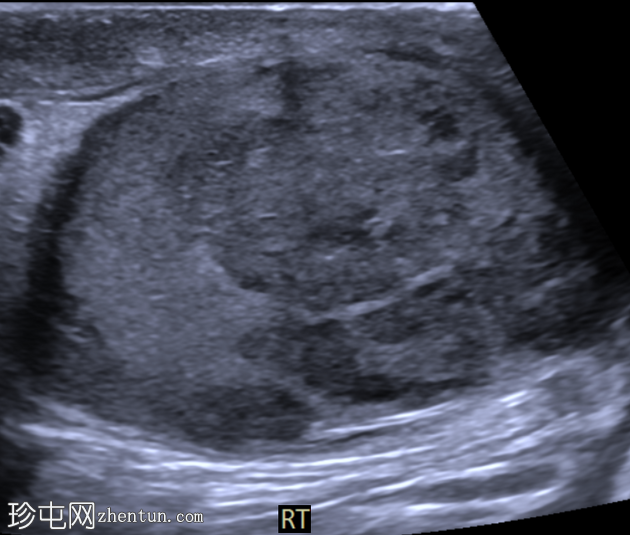

右侧睾丸内可见一大小约3.0 x 5.0 cm的异质性分叶状低回声肿块。肿块内未见囊性区域或钙化。彩色多普勒超声检查显示肿块内血流丰富。左侧睾丸正常。